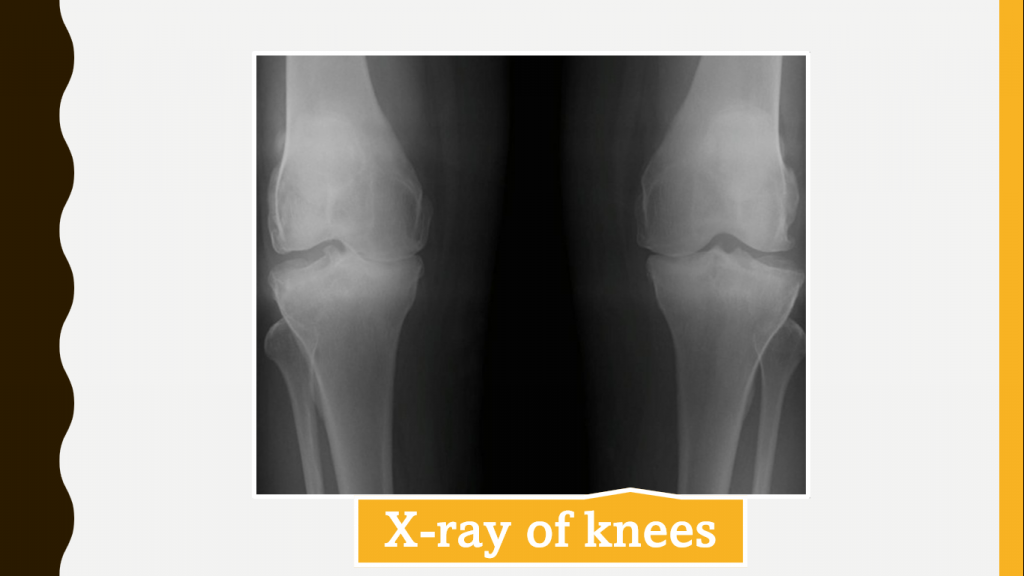

She had no significant wrist stiffness and limitation of movements of knees. Inflammatory parameters were normal and radiography of both hands and knees showed grade 3 osteoarthritis changes. The other diagnoses to be considered are rheumatoid arthritis and seronegative spondyloarthropathy.

As per ACR criteria (Table 1) for diagnosing osteoarthritis (OA) of the knee, the age of the patient is generally 50 years, but there is no age specification for hand OA (Table 2). The current patient had symptoms since the age of 37 and the joints involved were the knees and ankles. The pain had recently progressed to elbows and shoulders. The X-ray of knee joints was suggestive of radiological features of OA. The involvement of elbows and shoulders in OA is rare, hence the possibility of RA should be considered. The inflammatory parameters could be normal in the early stages of RA or with very low disease activity. To confirm the diagnosis, the patient was evaluated for anti-CCP and the result was negative. In India, the onset of OA is early and has been reported even in youngsters of ≤40 years of age. The patient is an agriculture labourer and the postures of work include cross-leg and squatting, the chance of OA is higher and occurs at an early age.